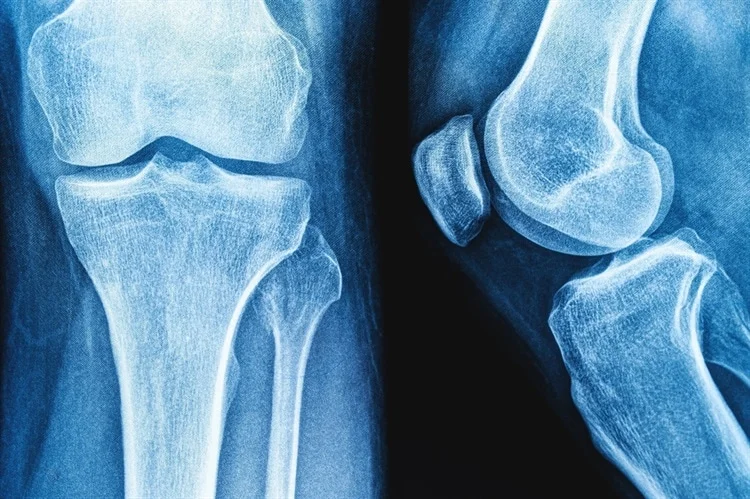

في مرحلة البلوغ، يتباطأ تكوين العظام بينما يزداد امتصاصها، مما قد يؤدي تدريجيًا إلى فقدان كتلة العظام، مما يؤدي إلى كسور هشاشة العظام.

يُعد الكالسيوم وفيتامين د والفوسفور ضروريين لصحة العظام ووظائفها الفسيولوجية. يُعد الزبادي مصدرًا جيدًا للبروتين والبوتاسيوم والكالسيوم والفيتامينات والزنك والسيلينيوم، والتي يُعرف الكثير منها بفوائدها في تعزيز صحة العظام ونموها.

أدت المستويات العالية من فيتاميني ك وب، وزيادة تأين المعادن في الزبادي مقارنةً بالحليب، إلى اقتراحات بأن الزبادي قد يساعد على تحسين صحة العظام والحفاظ عليها.

على وجه التحديد، وجدت إحدى الدراسات تأثيرًا وقائيًا على خطر الإصابة بهشاشة عظام الكعبرة لدى مستهلكي الزبادي بكثرة مقارنةً بغير المستهلكين، كما وجدت دراسة أخرى ارتفاعًا في كثافة المعادن في عظم الفخذ وكثافة المعادن في الورك لدى النساء اللواتي يتناولن الزبادي بأعلى كمية مقارنةً بمن يتناولنه بأقل كمية.